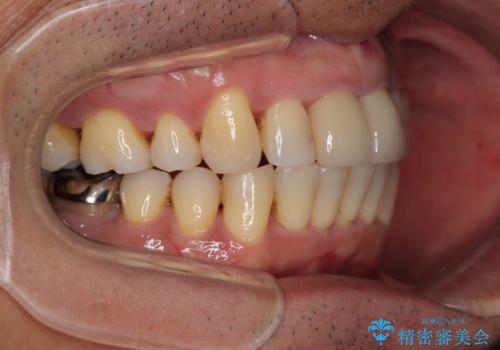

上顎前歯に装着されていた保険診療の前歯は見た目が気になるとのことであったので、矯正治療後にオールセラミッククラウンにて補綴治療を行うこととしました。

食いしばりにより奥歯がすり減っており、咬み合わせが定まるまで時間がかかりましたが、整った口もに仕上がりました。